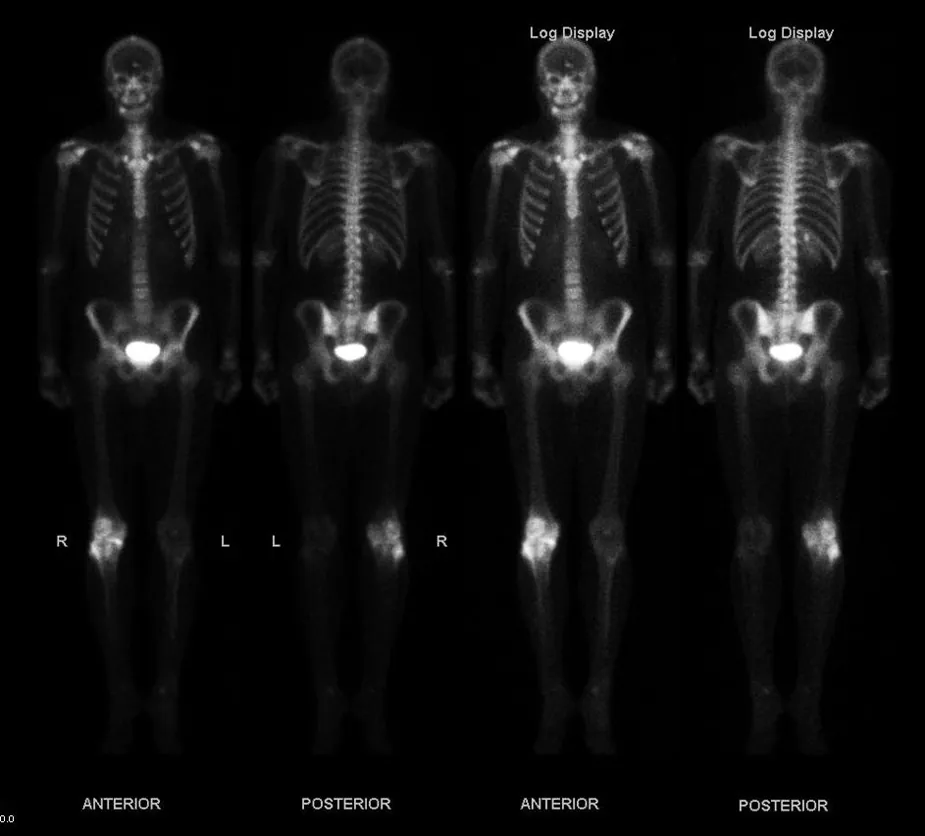

Alpha radiation from radioactive sources has a range much less than a millimeter of biological tissues, usually not enough to even penetrate the dead layers of our skin. On the other hand, the same αα radiation can penetrate a few centimeters of air, so mere distance from a source prevents αα size 12{α} {} radiation from reaching us. This makes αα size 12{α} {} radiation relatively safe for our body compared to ββ and γγ size 12{γ} {} radiation. Typical ββ radiation can penetrate a few millimeters of tissue or about a meter of air. Beta radiation is thus hazardous even when not ingested. The range of ββ size 12{β} {} s in lead is about a millimeter, and so it is easy to store ββ sources in lead radiation-proof containers. Gamma rays have a much greater range than either αα size 12{α} {}s or ββ size 12{β} {}s. In fact, if a given thickness of material, like a lead brick, absorbs 90% of the γγs, then a second lead brick will only absorb 90% of what got through the first. Thus, γγs do not have a well-defined range; we can only cut down the amount that gets through. Typically, γγ size 12{γ} {}s can penetrate many meters of air, go right through our bodies, and are effectively shielded (that is, reduced in intensity to acceptable levels) by many centimeters of lead. One benefit of γγ size 12{γ} {}s is that they can be used as radioactive tracers (see Figure 31.6).

This figure shows four images of a skeleton of a human. Different parts of the body show bright spots wherever the bone cells are most active, indicating bone cancer.

Figure 31.6 This image of the concentration of a radioactive tracer in a patient’s body reveals where the most active bone cells are, an indication of bone cancer. A short-lived radioactive substance that locates itself selectively is given to the patient, and the radiation is measured with an external detector. The emitted γγ size 12{γ} {} radiation has a sufficient range to leave the body—the range of αα size 12{α} {} s and ββ size 12{β} {} s is too small for them to be observed outside the patient. (credit: Kieran Maher, Wikimedia Commons)